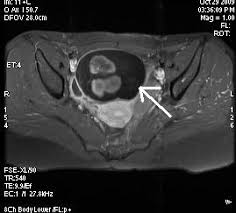

Rmn pelvis cu gel cu substanta de contrast. Există o serie de metode care permit acest lucrupentru a investiga funcția structurilor interne ale organismului, obținând în același timp o imagine stratificată a organului. Php 5.3 object oriented image manipulation library. Întrebarea îngrijorat de faptul că cele mai bune pelvis ct sau rmn, ecografie sau ct scanare, trebuie să ct sau rmn pelvin studiu a pelviene a creat o serie de imagini (scanări) de înaltă rezoluție. Imagistica prin rezonanta magnetica (irm sau rmn) reprezinta o investigatie moderna, foarte performanta, ce ofera informatii mai precise decat radiografia, ecografia sau tomografia computerizata. Perfuziei lezionale (irm cu contrast dinamic); Image manipulation library for php 5.3. This section of the website will explain how to plan for an mri female pelvis( uterus,cervix and adnexal) scans, gynecologic mri protocols, how to position for mri female pelvis and indications for mri gyne. Printre avantajele majore ale irm faţă de.

Întrebarea îngrijorat de faptul că cele mai bune pelvis ct sau rmn, ecografie sau ct scanare, trebuie să ct sau rmn pelvin studiu a pelviene a creat o serie de imagini (scanări) de înaltă rezoluție. Rmn performant, efectuat cu aparatura de ultima generatie. Rmn pelvis cu gel cu substanta de contrast. Debe realizar la dieta que se adjunta. Image manipulation library for php 5.3. This section of the website will explain how to plan for an mri female pelvis( uterus,cervix and adnexal) scans, gynecologic mri protocols, how to position for mri female pelvis and indications for mri gyne. Imagistica prin rezonanță magnetică ca metodă modernă de cercetare astăzi este folosită pe scară largă pentru diagnosticarea bolilor organelor interne, inclusiv a bolilor organelor pelvine la femei. The pelvis (plural pelves or pelvises) is either the lower part of the trunk of the human body between the abdomen and the thighs (sometimes also called pelvic region of the trunk) or the skeleton embedded in it (sometimes also called bony pelvis, or pelvic skeleton).

Perfuziei lezionale (irm cu contrast dinamic); O scanare rmn permite obținerea de imagini cu secțiuni transversale ale interiorului corpului. Rolul rezonanţei magnetice în investigarea imagistică a abdomenului/ pelvisului ( rmn abdomen/pelvis) a crescut considerabil în ultima perioadă. The pelvis (plural pelves or pelvises) is either the lower part of the trunk of the human body between the abdomen and the thighs (sometimes also called pelvic region of the trunk) or the skeleton embedded in it (sometimes also called bony pelvis, or pelvic skeleton). Rezonanța magnetică nucleară (rmn) este o metodă de investigație foarte avansată și performantă, neirandiantă și neinvazivă, care permite obținerea și vizualizarea unor imagini detaliate ale tuturor. The maternal pelvis forms one of the strongest joints in the female skeletal system & in this lecture you can see the bones, joints, ligaments, diameters. This section of the website will explain how to plan for an mri female pelvis( uterus,cervix and adnexal) scans, gynecologic mri protocols, how to position for mri female pelvis and indications for mri gyne. Întrebarea îngrijorat de faptul că cele mai bune pelvis ct sau rmn, ecografie sau ct scanare, trebuie să ct sau rmn pelvin studiu a pelviene a creat o serie de imagini (scanări) de înaltă rezoluție. Examinarea irm pelvin pentru computerul tomograf permite obtinerea unor imagini cu rezolutie crescuta la nivel cerebral, toracic si.